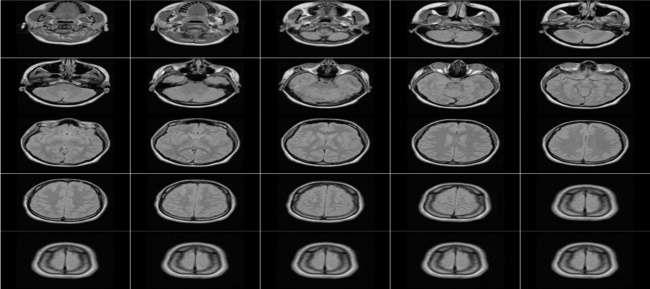

The proposed method applied on DICOM image of brain that consists of 25 slices, each slice consists of 2d matrix (256×256), each pixel represented by integer (16-bits). Figure 9 explain all DICOM slices of used image. The use of DICOM images is common in medical imaging, and the encryption of these images is important for ensuring patient privacy and data security. By applying the proposed method to a DICOM image of the brain, the authors demonstrate the effectiveness of their approach in encrypting complex and sensitive medical data.

Figur 9. An example of DICOM slicse Figure 10. Results of row permutation Figure 11. Results of the columns permutation